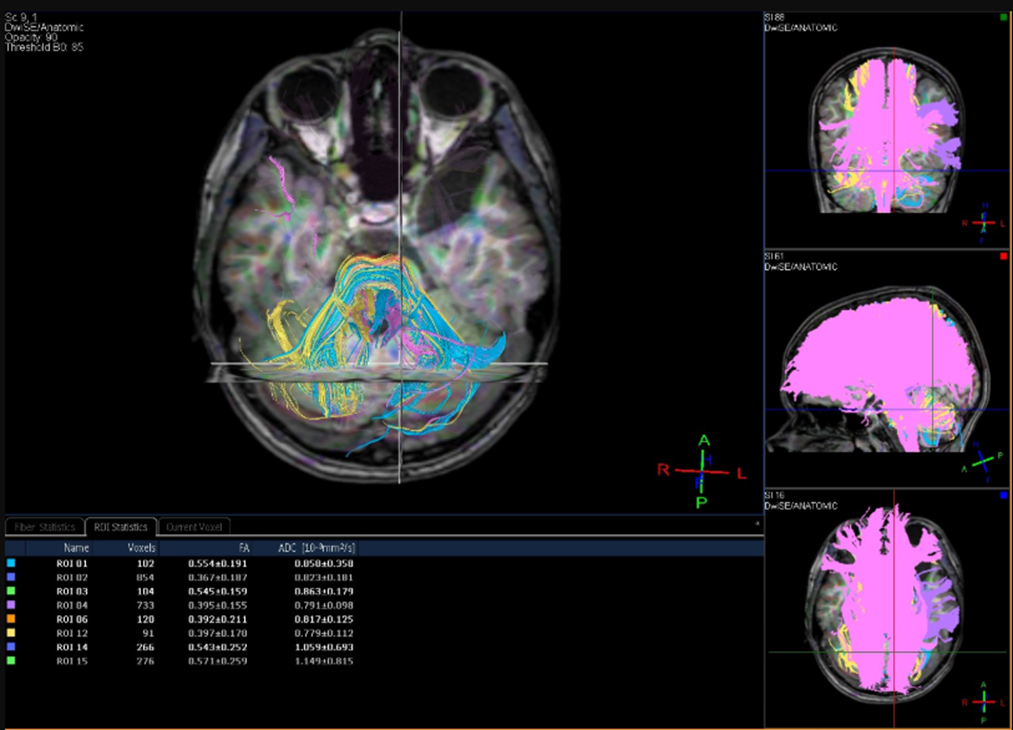

EEG in awakening was performed before the treatment and demonstrated the sharp-wave elements in the following zones: right frontocentral, right central-parietal, with impulse conductivity to the left frontocentral and vertex zones. The single episodes of diffuse spread of epiactivity lasting up to 1 second are shown during this investigation. The index of epileptiform activity is low/medium and the greatest presentation is during child’s falling asleep. According to the results of MRI of the brain and diffusion tensor MR imaging before treatment (Philips Ingenia 3T magnetic resonance tomograph):

1) the architectonics of the corpus callosum associative fibers is unchanged, whereas the average FA values remain within the age norm - (FA) 0.413+/-0.207;

2) the arcuate fasciculus fibers between Wernicke's and Broca's areas are clearly visualized; their architectonics is not disrupted; the FA values are moderately reduced 0.397+/-0.179 (n-0.450+/-0.08), which may lead to impaired connectivity of expressive-receptive speech areas (impact on the child’s ability to reproduce language sounds and perceive such sounds as linguistically significant);

3) the corticospinal tracts are relatively symmetrical and their architectonics is not affected, the average anisotropy indicators are without any deviations from the normal range: right - (FA) 0.454+/-0.199, left - (FA) 0.471+/-0.201.

Figure 2: Diffusion tensor MR imaging findings before treatment.

MR signs of arachnoid cyst in the left temporal-polar zone (type I after Galassi). The changes at the level of the left hippocampus are corresponding to Incomplete Hippocampal Inversion (IHI). No volumetric-focal pathology in the brain was detected during the examination. A moderate decrease in the average FA does not exclude a “violation of connectivity” between Wernicke's and Broca's areas (impact on the child’s ability to reproduce speech sounds and perceive them as linguistically significant). The results of routine laboratory blood tests prior to treatment did not show any significant deviations from the reference values. The results of biochemical blood tests revealed a preliminarily increased level of alkaline phosphatase (286.6 U/l; RR 53-128 U/l) and total creatinine phosphokinase (198.4 mmol/l; RR <171>

Figure 3: Diffusion tensor MR imaging findings before treatment.